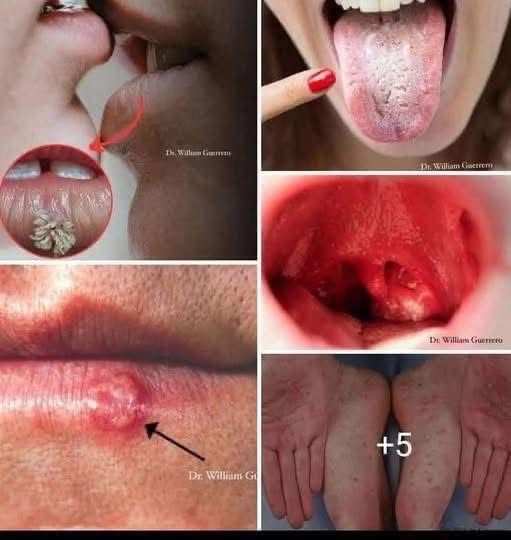

Whatever the reason behind a bite, it is important to handle the aftermath properly. Treating a cat bite should never be taken lightly. Because cats’ teeth are sharp and can puncture deeply, bacteria may be introduced under the skin, increasing the risk of infection. Immediately wash the wound with soap and water, apply antiseptic, and cover with a clean bandage. If the bite is deep, swollen, or painful, seek medical attention promptly.